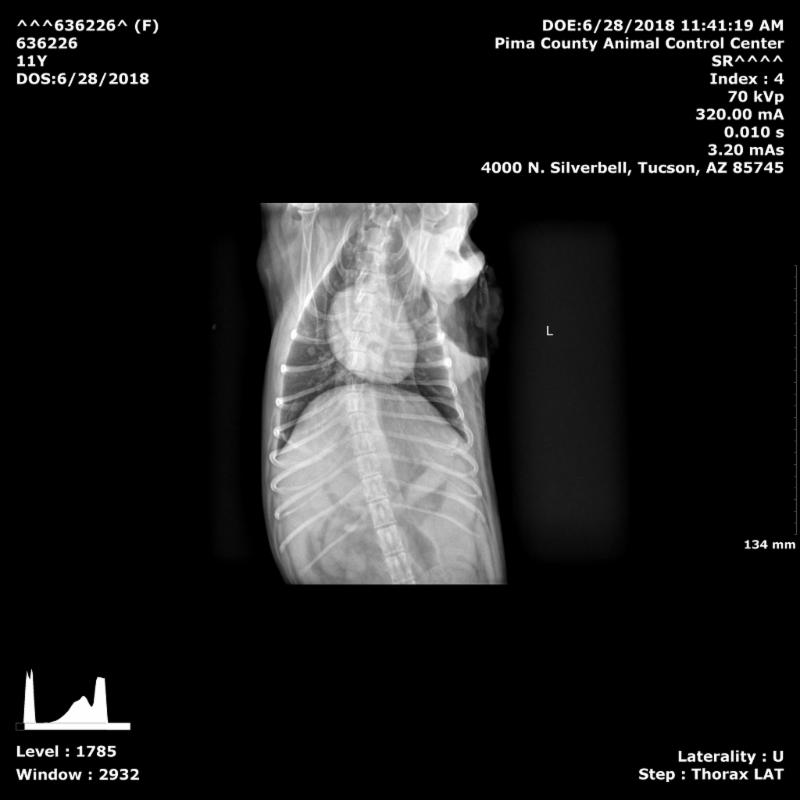

Dr. Brett did an ultra sound and lung X-rays (at a major discount which made it worth the four hour drive up there.) We discussed the pathology report I brought up for his review and after reading it and performing his examination on Mini, he suggested not doing any surgery.

While Mini's organs - liver, spleen, kidneys and on X-rays the lungs- did not show evidence of tumors, which as great news....all was not good.

Dr. Monika here in Benson will be doing another complete blood work in a month and again in three months, sending results up to Dr. Hershey. If all is going as well as hoped, Mini will go back up to see Dr. Hershey (we have an appointment for November 19th) to have another ultrasound and X-rays to see whether the cancer is spreading, and whether the size of the lymph nodes and tumors is - hopefully! - being reduced by the medications.